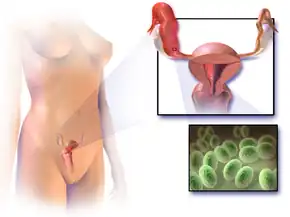

Pelvic inflammatory disease, also known as pelvic inflammatory disorder (PID), is an infection of the upper part of the female reproductive system, namely the uterus, fallopian tubes, and ovaries, and inside of the pelvis.[5][2] Often, there may be no symptoms.[1] Signs and symptoms, when present, may include lower abdominal pain, vaginal discharge, fever, burning with urination, pain with sex, bleeding after sex, or irregular menstruation.[1] Untreated PID can result in long-term complications including infertility, ectopic pregnancy, chronic pelvic pain, and cancer.[2][3][4]

The disease is caused by bacteria that spread from the vagina and cervix.[5] Infections by Neisseria gonorrhoeae or Chlamydia trachomatis are present in 75 to 90 percent of cases.[2] Often, multiple different bacteria are involved.[2] Without treatment, about 10 percent of those with a chlamydial infection and 40 percent of those with a gonorrhea infection will develop PID.[2][9] Risk factors are generally similar to those of sexually transmitted infections and include a high number of sexual partners and drug use.[2] Vaginal douching may also increase the risk.[2] The diagnosis is typically based on the presenting signs and symptoms.[2] It is recommended that the disease be considered in all women of childbearing age who have lower abdominal pain.[2] A definitive diagnosis of PID is made by finding pus involving the fallopian tubes during surgery.[2] Ultrasound may also be useful in diagnosis.[2]

Chlamydia trachomatis and Neisseria gonorrhoeae are usually the main cause of PID. Data suggest that PID is often polymicrobial.[14] Isolated anaerobes and facultative microorganisms have been obtained from the upper genital tract. N. gonorrhoeae has been isolated from fallopian tubes, facultative and anaerobic organisms were recovered from endometrial tissues.[17][18]

The anatomical structure of the internal organs and tissues of the female reproductive tract provides a pathway for pathogens to ascend from the vagina to the pelvic cavity thorough the infundibulum. The disturbance of the naturally occurring vaginal microbiota associated with bacterial vaginosis increases the risk of PID.[17]